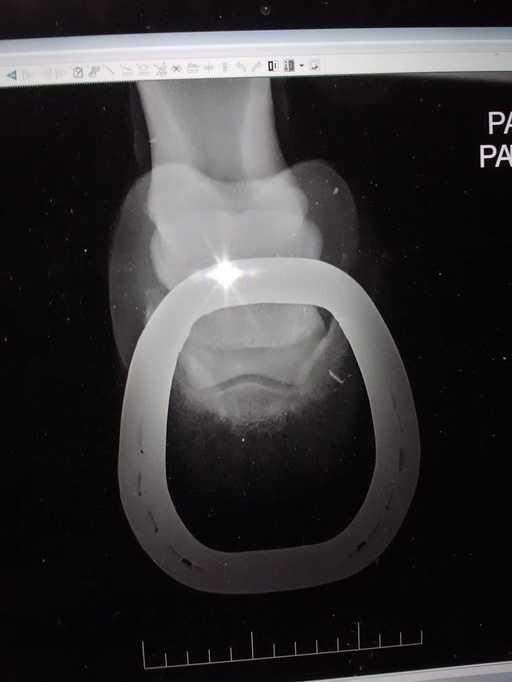

8. 这是马的脚!

一些奇怪的X光照片,看完整个人都不好了……-8.jpg